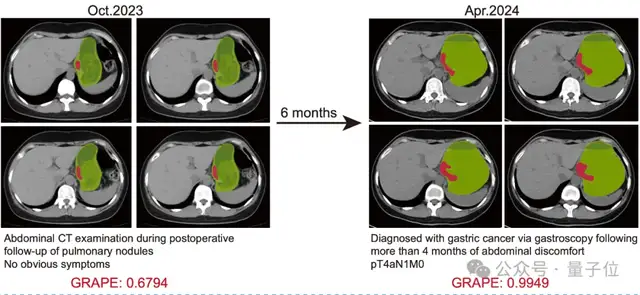

论文共同一作、浙江省肿瘤医院胃外科博士胡灿提到,2024年4月,一名患者检测出局部晚期胃癌。医生对其进行回溯研究时,将其6个月前检查其他疾病做过的平扫CT影像喂给DAMO GRAPE,就提示其存在早期胃癌病灶。

假使当时就有AI自动检测,这名患者将提前6个月确诊并接受治疗。

△AI提前6个月识别出胃癌

这并非个例,在此次研究中,共回顾了11名患者确诊前的CT影像,发现AI可提前2到10个月不等检测出胃癌。